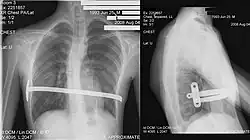

His two-stage procedure, widely known as the Nuss procedure, involves slipping in one or more concave steel bars into the chest, underneath the sternum.[63]

The bar is flipped to a convex position so as to push outward on the sternum, correcting the deformity. The bar usually stays in the body for about two years.[53][64] When the bones have solidified into place, the bar is removed through outpatient surgery.

Although initially designed to be performed in younger children of less than 10 years of age, whose sternum and cartilage is more flexible, there are successful series of Nuss treatment in patients well into their adult life.[63][64][65]